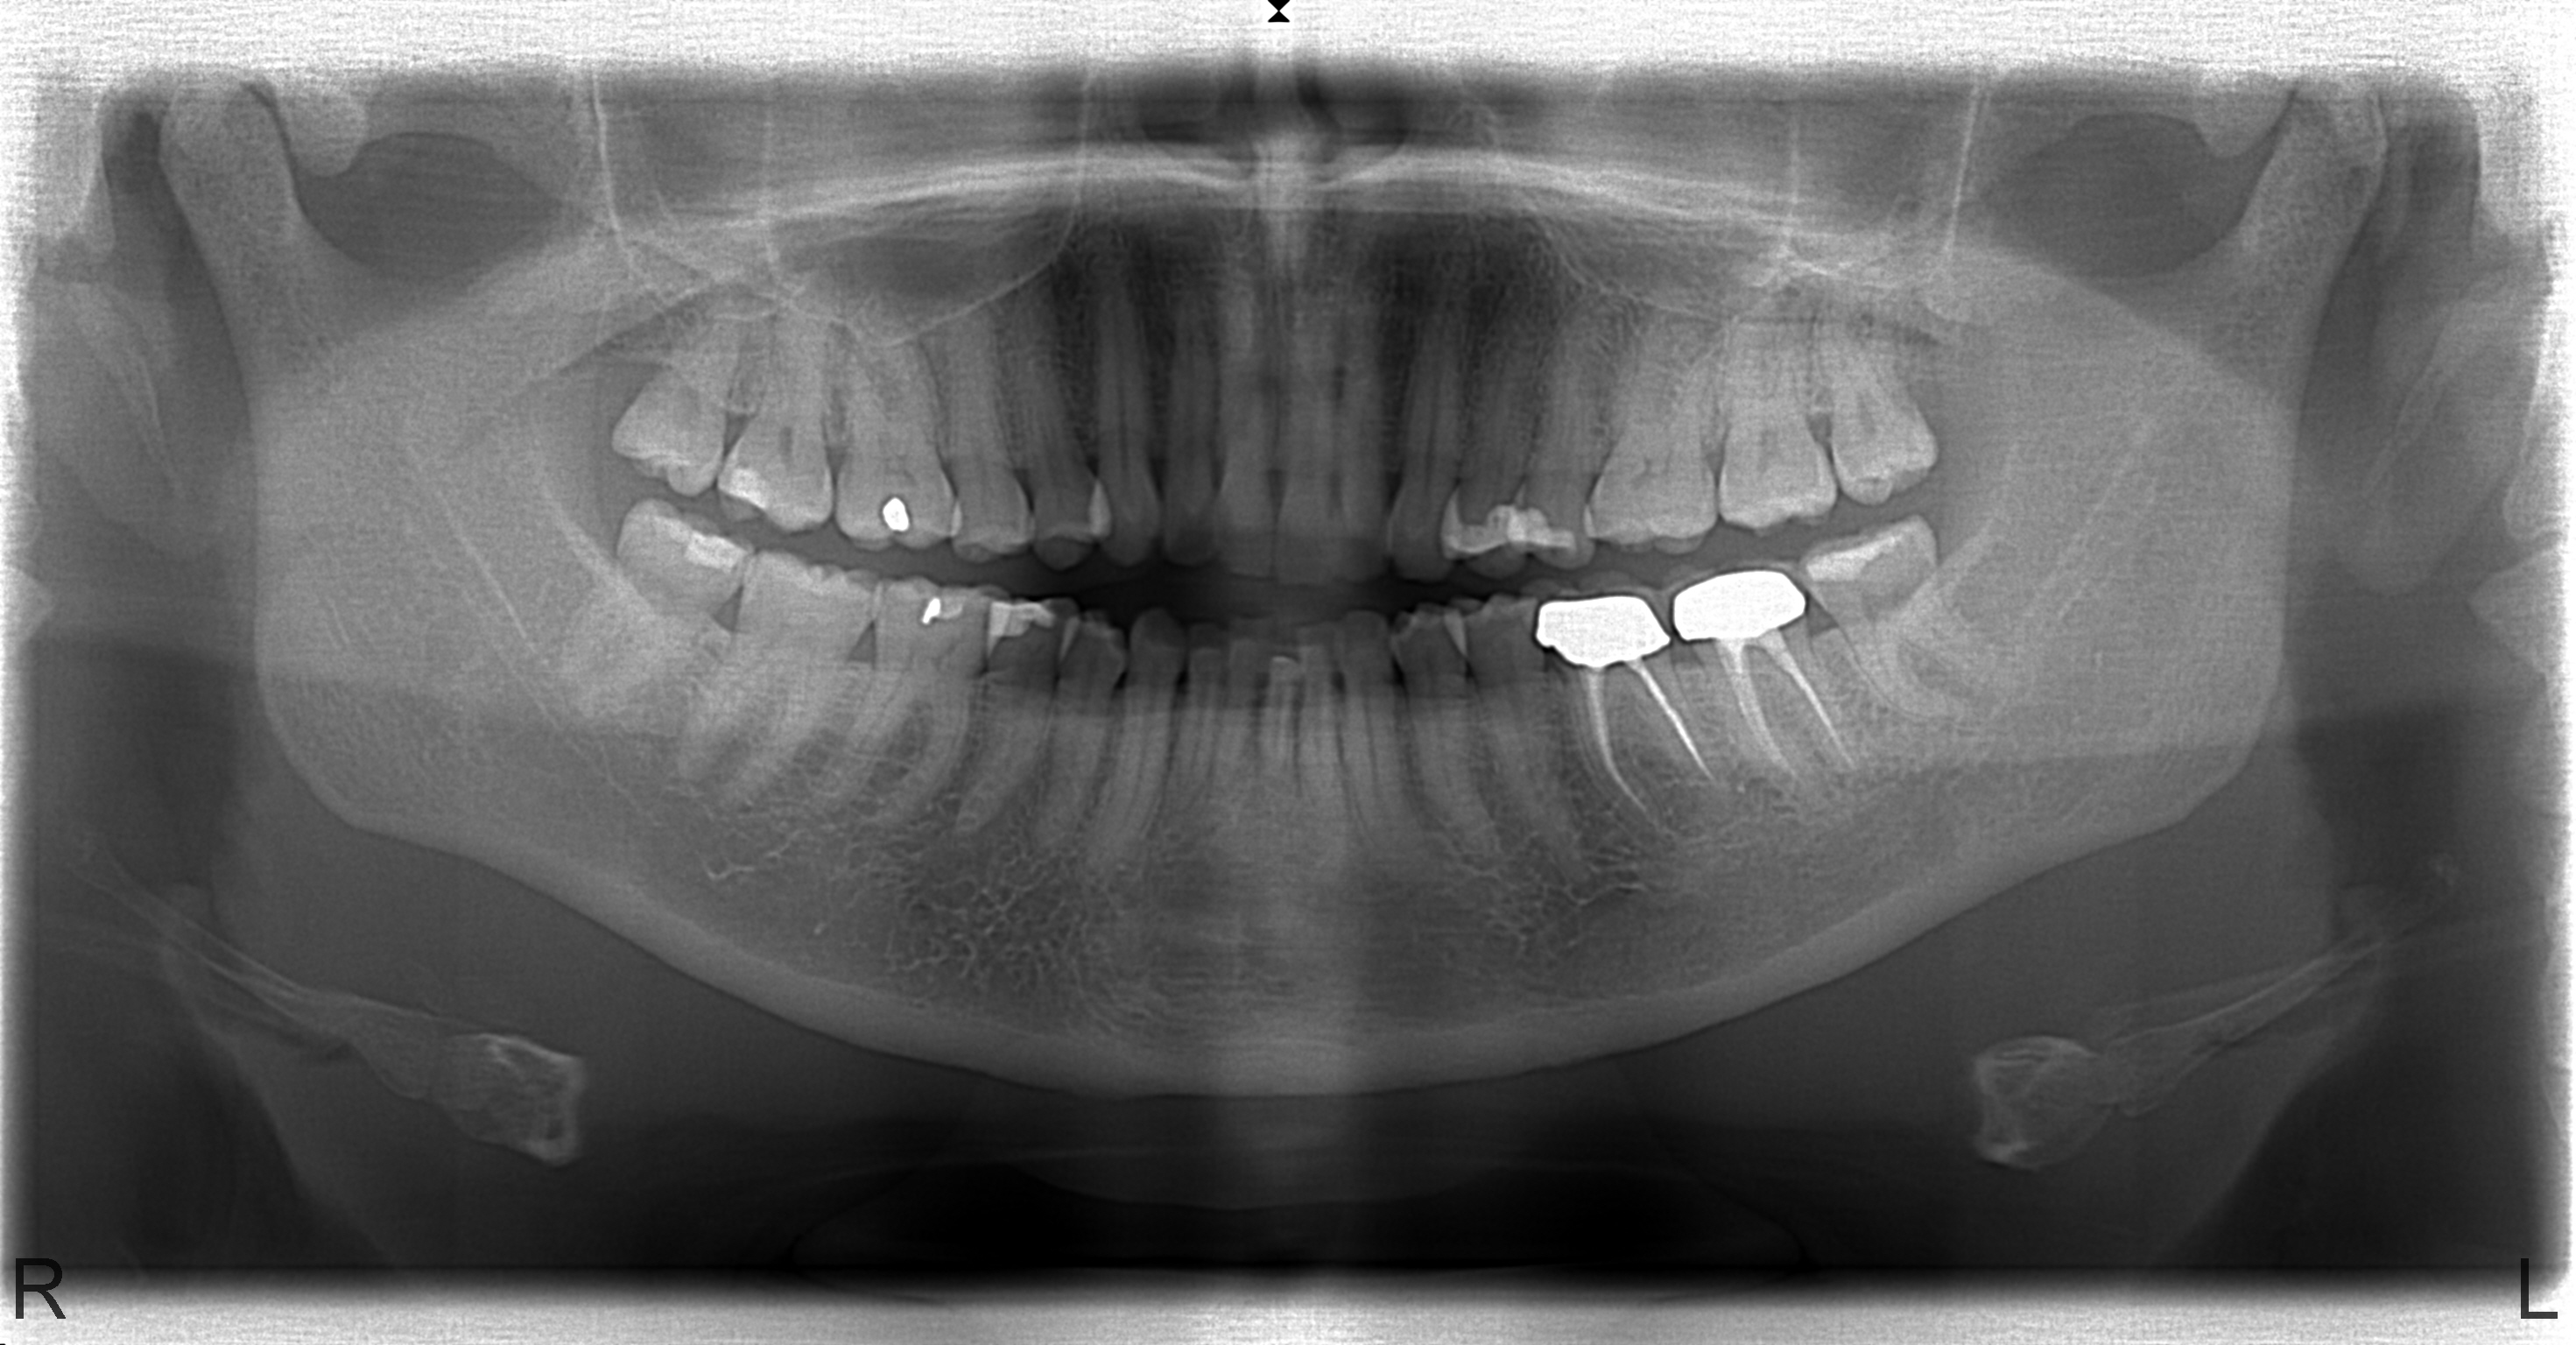

Al enige tijd ben ik (44) aan een beugel aan het denken en nu eindelijk de foto's gemaakt.

Mijn angst is dat het gebied rondom mijn kronen heel erg gevoelig wordt. ik merk nu ook al dat de kronen kwetsbaarder zijn dan de rest van mijn tanden (soms steken).

Nu denk ik dat er best wel wat druk op deze kronen komt te liggen. Ze liggen immers naast elkaar en de kiesjes naast de snijtand worden allevier getrokken om ruimte te maken. (Mijn voor- en ondertanden moeten dus naar achter).